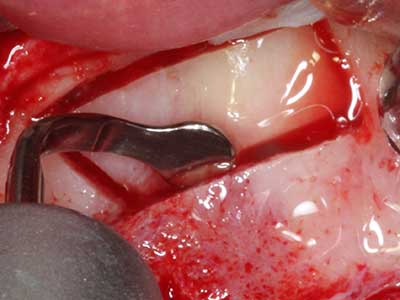

Fig. 1: preparazione di una copertura ossea con Piezomed (W&H Salisburgo, Austria).

Fig. 3: la separazione basale del blocco è più semplice con i raccordi appositamente angolati.